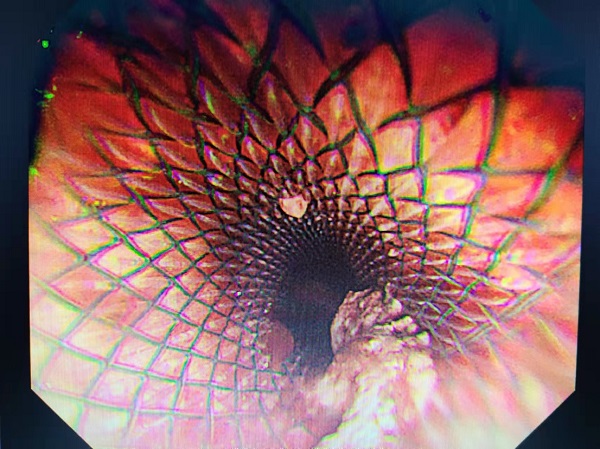

图:食管管腔(手术后)

通过支架植入,患者可以依靠支架的弹性作用,扩张狭窄部位,膜阻止肿瘤向管腔内生长,术中选择超过病灶长度的支架,使支架在病灶两端均突出1-2cm,防止肿瘤生长超过支架,再次堵塞管腔,从而延长支架的作用时间。当天手术顺利,患者可以进食,达到了手术预期效果。

内三科杨德仲医生介绍说,胃镜下覆硅胶膜食道支架植入术对患者创伤小、恢复快,通过扩张狭窄部位,迅速解除梗阻,对失去手术时机的中晚期消化道肿瘤引起的梗阻患者带来便利,进一步改善晚期癌症病人的生活质量,延长生存期。